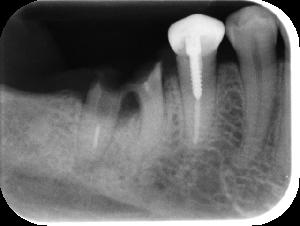

レントゲンのよる検査

表面からみただけではわからない歯や歯槽骨の状態を調べます。あごの状態も確認します。